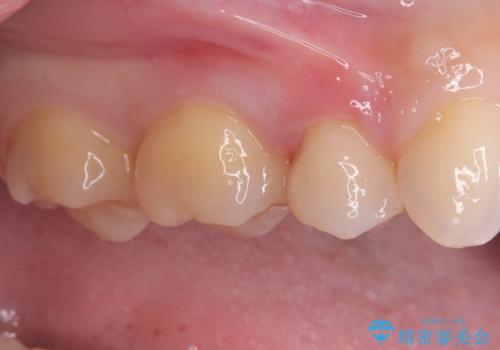

見逃しやすい小さな穴も精密に修復。自然な見た目のセラミックインレー

- 右上5番(小臼歯)の咬み合わせの面(咬合面)に小さな穴があることを主訴にご来院されました。視診およびレントゲン検査の結果、表面の穴は小さいものの、内部で虫歯が広がっていることが確認されました。患者様から「目立たないように治したい」というご希望があったため、健全な歯質を極力残しながら、審美性と耐久性に優れた**セラミックインレー(詰め物)**で修復する計画を立案しました。

後日、歯の色調に合わせてオーダーメイドで作製されたセラミックインレーを装着。セラミックは天然歯のような透明感があるため、修復した箇所がどこかわからないほど自然な仕上がりとなりました。